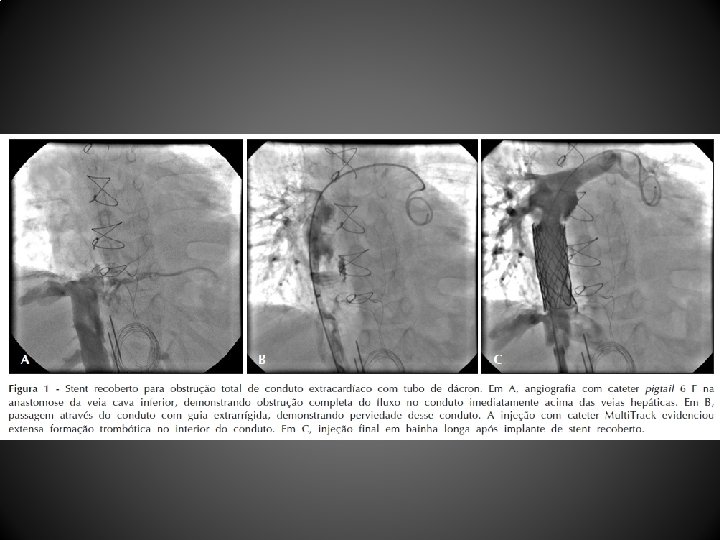

Introdução • A introdução da cirurgia de anastomose cavopulmonar total (ACPT) ou cirurgia de Fontan modificou de forma significativa a história natural de pacientes com cardiopatias complexas não passíveis de reparo biventricular • É conhecido o desenvolvimento de estenoses silenciosas por utilização de condutos fenestrados • O estudo relata a experiência de um centro terciário no implante percutâneo de dispositivos em condutos de pacientes com circulação do tipo univentricular

Método • Entre julho de 2000 e julho de 2010, 12 pacientes receberam dispositivos percutâneos em condutos após cirurgia de Fontan • Os pacientes foram divididos em dois grupos, de acordo com a indicação para o procedimento: - Grupo I: 5 pacientes receberam implante de oclusores septais para fechamento de fenestração cirúrgica - Grupo II: 6 pacientes receberam stents para alívio de obstrução de condutos , - 1 paciente recebeu ambos os dispositivos simultaneamente

Procedimento e técnica • Implante de stents em condutos • Acesso femoral obtido em 6 pacientes e acesso jugular em 2 pacientes por obstrução venosa femoral crônica • Após criterioso estudo manométrico e anatômico, bainha longa introduzida através do conduto sobre guia extrarrígida e avanço do stent montado manualmente em balão com diâmetro previamente escolhido e insuflado para desobstrução do conduto e/ou oclusão de fenestração, no caso de stents recobertos • Todos os pacientes receberam heparina (100 UI/kg) e profilaxia com antibióticos endovenosos

Resultados • Grupo I: saturação média passou de 82, 6 + 7, 5% para 90, 4 + 7, 5% logo após o procedimento (P = 0, 001) • Grupo II: saturação média passou de 81, 8 + 8, 9% para 91, 3 + 8, 7% (P = 0, 01) • Menor diâmetro do conduto passou de uma média de 6, 9 + 4, 8 mm para 16, 6 + 3, 5 mm após o procedimento (P = 0, 02) • Paciente que realizou ambos os procedimentos simultaneamente teve aumento do menor diâmetro do conduto de 11, 7 mm para 16 mm e melhora da saturação sistêmica, passando de 60% para 90%